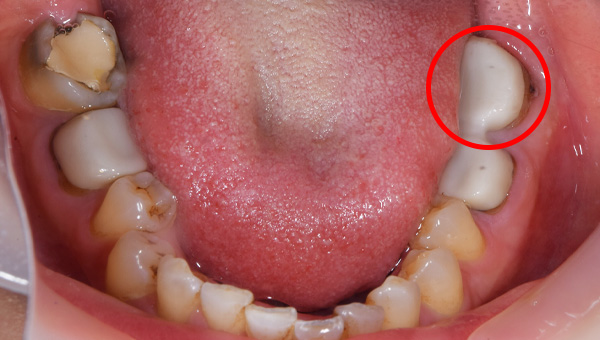

初診時のパノラマレントゲン

説明:

初診時のパノラマレントゲンです。右上の歯が虫歯によって大きく欠けているのがわかります。

歯が大きく欠けた

歯ぐきが治癒した

右上の歯が大きく欠けています。黒く虫歯になっているのがわかります。移植を計画しましたので、歯ぐきがしっかり治癒するのを(1ヶ月)待ちました。